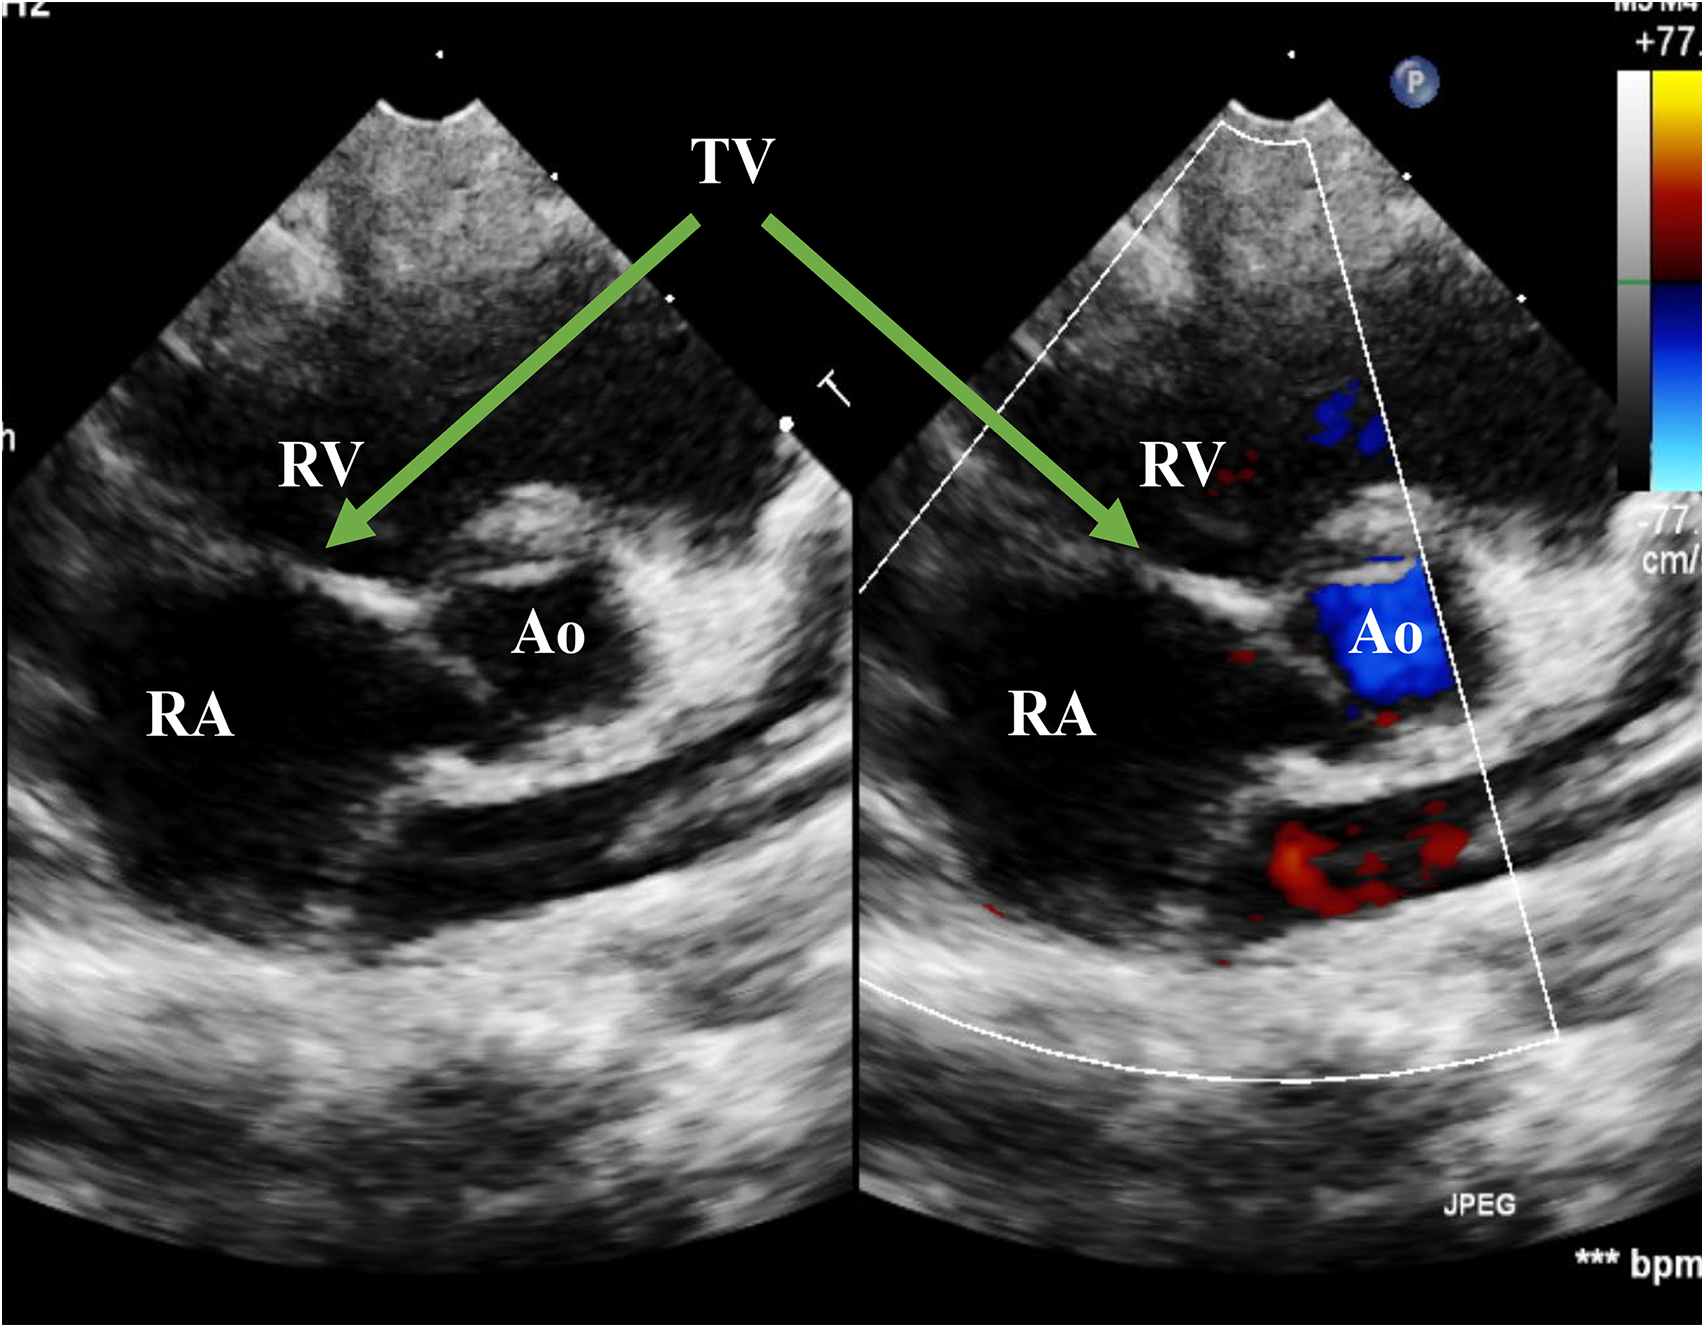

Figure 5

Echo at the latest visit in the PSAX view. The figure showed good coaptation of the TV in the systolic phase. PSAX, parasternal short-axis view; RA, right atrium; RV, right ventricle; Ao, Aorta; TV, tricuspid valve

Figure 6

Echo at the latest visit in the A4C view. The figure showed normal movement of the anterior leaflet of the TV in the systolic phase. RA, right atrium; RV, right ventricle; TV, tricuspid valve; A4C, apical four-chamber.

The patient was weaned from mechanical ventilation 12 h after surgery and left the cardiac intense care unit (CICU) on the fourth day after surgery (Figure 4). Inotropic and nitro oxide were not needed after surgery. An Echo before discharge indicated no deterioration of TR, with coordinated movement during the cardiac cycle. ECG before discharge indicated complete right bundle branch block (CRBBB). The critical signs of the patient during the process of management are shown in Figure 3, indicating a quick improvement in oxygen saturation after surgery (Figure 4). The last visit at 4 months old showed normal biventricular function and mild TR (Figures 5, 6).